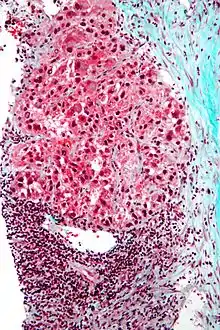

Micrograph of hepatocellular carcinoma. Liver biopsy. Trichrome stain.

Macroscopically, liver cancer appears as a nodular or infiltrative tumor. The nodular type may be solitary (large mass) or multiple (when developed as a complication of cirrhosis). Tumor nodules are round to oval, gray or green (if the tumor produces bile), well circumscribed but not encapsulated. The diffuse type is poorly circumscribed and infiltrates the portal veins, or the hepatic veins (rarely).[17]

Microscopically, the four architectural and cytological types (patterns) of hepatocellular carcinoma are: fibrolamellar, pseudoglandular (adenoid), pleomorphic (giant cell), and clear cell. In well-differentiated forms, tumor cells resemble hepatocytes, form trabeculae, cords, and nests, and may contain bile pigment in the cytoplasm. In poorly differentiated forms, malignant epithelial cells are discohesive, pleomorphic, anaplastic, and giant. The tumor has a scant stroma and central necrosis because of the poor vascularization.[41] A fifth form – lymphoepithelioma like hepatocellular carcinoma – has also been described.[42][43]